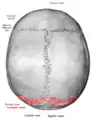

Lambdoid suture

The lambdoid suture (or lambdoidal suture) is a dense, fibrous connective tissue joint on the posterior aspect of the skull that connects the parietal bones with the occipital bone. It is continuous with the occipitomastoid suture.

![]() Lambdoid suture (labeled at bottom right) | |

The lambdoid suture is between the paired parietal bones and the occipital bone of the skull. It runs from the asterion on each side.

The lambdoid suture is named due to its uppercase lambda-like shape.

Skull seen from behind. Showing Λ-like shape of the lambdoid suture.